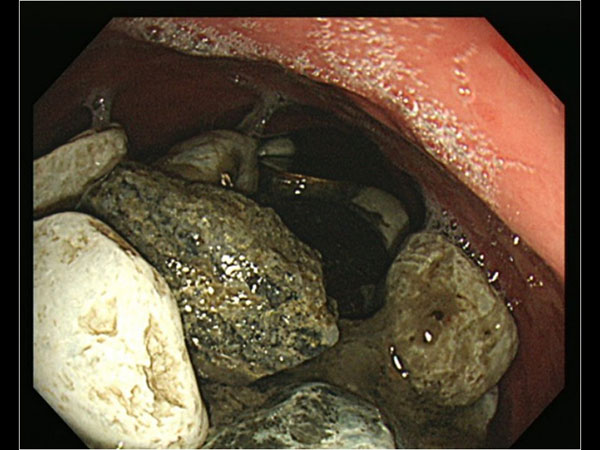

ಆಸ್ಪತ್ರೆಗೆ ಚಿಕಿತ್ಸೆಗೆಂದು ಬಂದ ವ್ಯಕ್ತಿಯ ಹೊಟ್ಟೆಯು ಉಬ್ಬರಗೊಂಡಿತ್ತು ಮತ್ತು ಹೊಟ್ಟೆಯನ್ನು ವೈದ್ಯರು ಮುಟ್ಟಿ ನೋಡಿದ ವೇಳೆ ಸಣ್ಣ ಸಣ್ಣ ಕಲ್ಲುಗಳು ಪತ್ತೆಯಾಗಿದೆ. ಮತ್ತಷ್ಟು ಪರಿಶೀಲನೆ ನಡೆಸಿದ ವೇಳೆ ವೈದ್ಯರಿಗೆ ಆಘಾತ ಉಂಟಾಯಿತು. ಯಾಕೆಂದರೆ ಆ ವ್ಯಕ್ತಿಯ ಹೊಟ್ಟೆಯೊಳಗಡೆ ಸಣ್ಣ ಸಣ್ಣ ಕಲ್ಲುಗಳು, ಬಾಟಲಿಯ ಮುಚ್ಚಳ ಇತ್ಯಾದಿಗಳು ಕಂಡುಬಂದವು. ಇದು ಸಂಪೂರ್ಣ ಹೊಟ್ಟೆಯನ್ನು ವ್ಯಾಪಿಸಿತ್ತು.

ಈ ವ್ಯಕ್ತಿಯನ್ನು ತಕ್ಷಣವೇ ಶಸ್ತ್ರಚಿಕಿತ್ಸೆ ಮಾಡಲಾಯಿತು ಮತ್ತು ವೈದ್ಯರ ಪ್ರಕಾರ ಇದು ತುಂಬಾ ಕಠಿಣ ಶಸ್ತ್ರಚಿಕಿತ್ಸೆಯಾಗಿತ್ತು. ಯಾಕೆಂದರೆ ಇಂತಹ ಶಸ್ತ್ರಚಿಕಿತ್ಸೆಯು ತುಂಬಾ ಕಠಿಣವಾಗಿರುವುದು ಮತ್ತು ಗ್ಯಾಸ್ಟ್ರೋಸ್ಕೋಪಿ ಮೂಲಕವಾಗಿ ಇದನ್ನು ತೆಗೆಯಬೇಕಾಯಿತು. ಬಾಯಿಯ ಮೂಲಕವಾಗಿ ತುಂಬಾ ತೆಳುವಾದ ಟ್ಯೂಬ್ ನ್ನು ಹಾಕಲಾಯಿತು. ಇದರ ಬಳಿಕ ತುಂಬಾ ಭಿನ್ನವಾಗಿರುವಂತಹ ಶಸ್ತ್ರಚಿಕಿತ್ಸೆ ವಿಧಾನದ ಮೂಲಕ ಹೊಟ್ಟೆಯಲ್ಲಿ ಇದ್ದ ಕಲ್ಲುಗಳು ಹಾಗೂ ಇತರ ಸಾಮಗ್ರಿಗಳನ್ನು ಹೊರಗೆ ತೆಗೆಯಲಾಯಿತು.